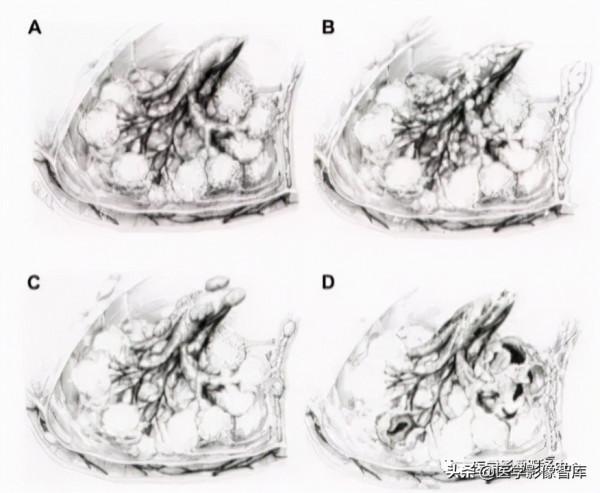

圖1:肺⼩葉模式圖

肺⼩葉(SPL)是肺的解剖功能基本單位,在討論各種CT掃描徵象之前,⾸先要認識肺⼩葉的基本結構及其在⾼解析度CT 掃描影象上的影像表現。SPL是肺亞節段⽔平的基本單位(圖1),周圍有纖維隔,稱為⼩葉間隔。SPL是不規則的多邊型,⼤⼩約為1 - 1.25cm,包含約12個肺腺泡。肺泡由呼吸性細⽀⽓管供應,構成參與⽓體交換的⼤肺單位。“⼩葉狀”細⽀⽓管(前末梢或末梢細⽀⽓管)、伴發的肺⼩動脈和⽀⽓管⾎管周圍間質內的中央淋巴管構成了SPL的⼩葉中⼼或核⼼結構。肺靜脈和淋巴管流⼊胸膜下叢,包含在⼩葉間隔內。

圖2. A正常⼩葉;B癌性淋巴管炎;C結節病;D淋巴管肌瘤病

圖3. A癌性淋巴管炎;B結節病;C淋巴管肌瘤病

HRCT掃描能夠識別出SPL的三個基本組成部分:⼩葉實質、⼩葉中⼼結構和⼩葉間隔。這些結構可因不同的疾病⽽產⽣差異,形成不同的模式。其中⼀些模式已被描述為影像的“徵象”,如樹芽徵,鋪路徵和頭芝⼠頭徵,⽽其他已被⽤來描述與特定疾病相關的病理。例如,淋巴管癌病表現為⼩葉間隔平滑或呈珠狀增厚,結節病表現為不規則的淋巴管周圍型分佈,淋巴管平滑肌瘤病表現為⼩葉囊腫形成(圖2,3A-D)。根據病變的解剖部位分佈特點,胸部CT徵象,可⼤致分為四部分:實質徵象、⽓道徵象、⾎管徵象和胸膜徵象。